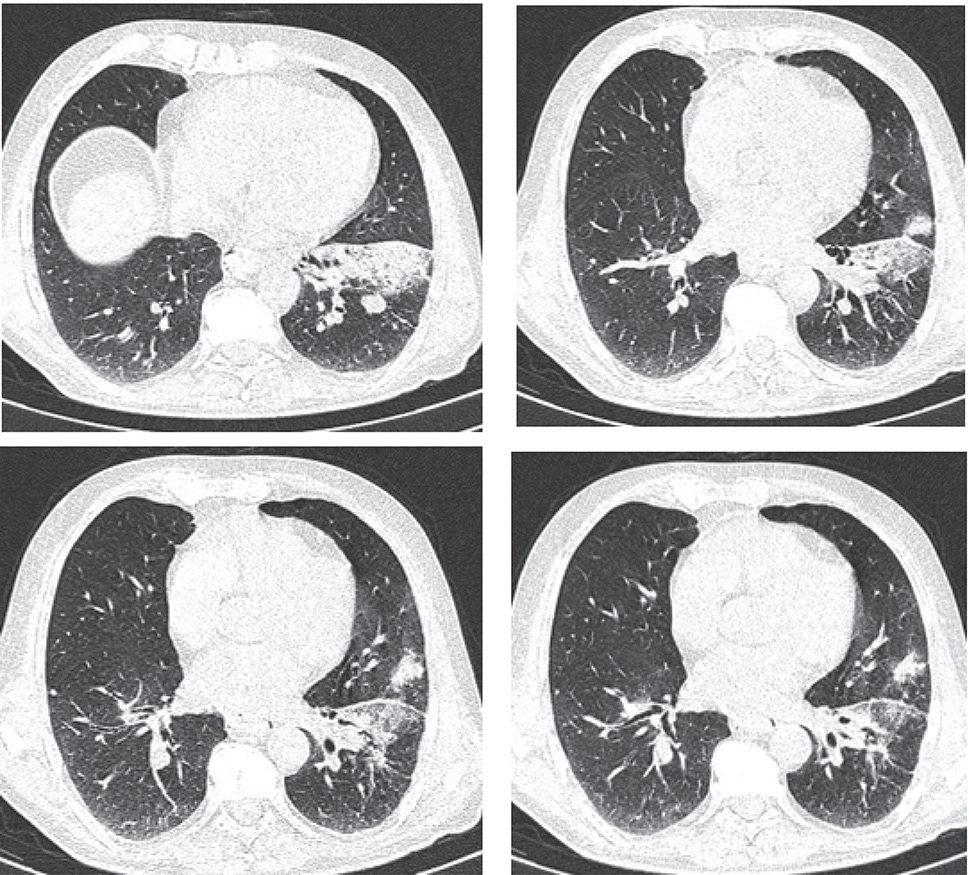

结核病好发部位为上叶尖段和下叶背段,其病变以结节影、斑片及小斑片样实变影为主 [9](图 3);肺炎患者 CT 影像显示新出现的斑片状浸润影、叶或段实变影、磨玻璃影或间质性改变 [10](图 4)。肺结核由结核杆菌引起,病理特征为结核结节、干酪样坏死等,早期炎症渗出与肺炎的肺泡内炎性渗出在影像学上难以区分。肺炎由细菌、病毒等感染所致,病理以肺泡实变为主,若病变范围小或不典型,也易与肺结核混淆。

注:患者女,50 岁,左肺上叶舌段及下叶片状实变影,其内见支气管走形,左侧叶间胸膜增厚。

图 4 肺炎患者 CT 扫描图像